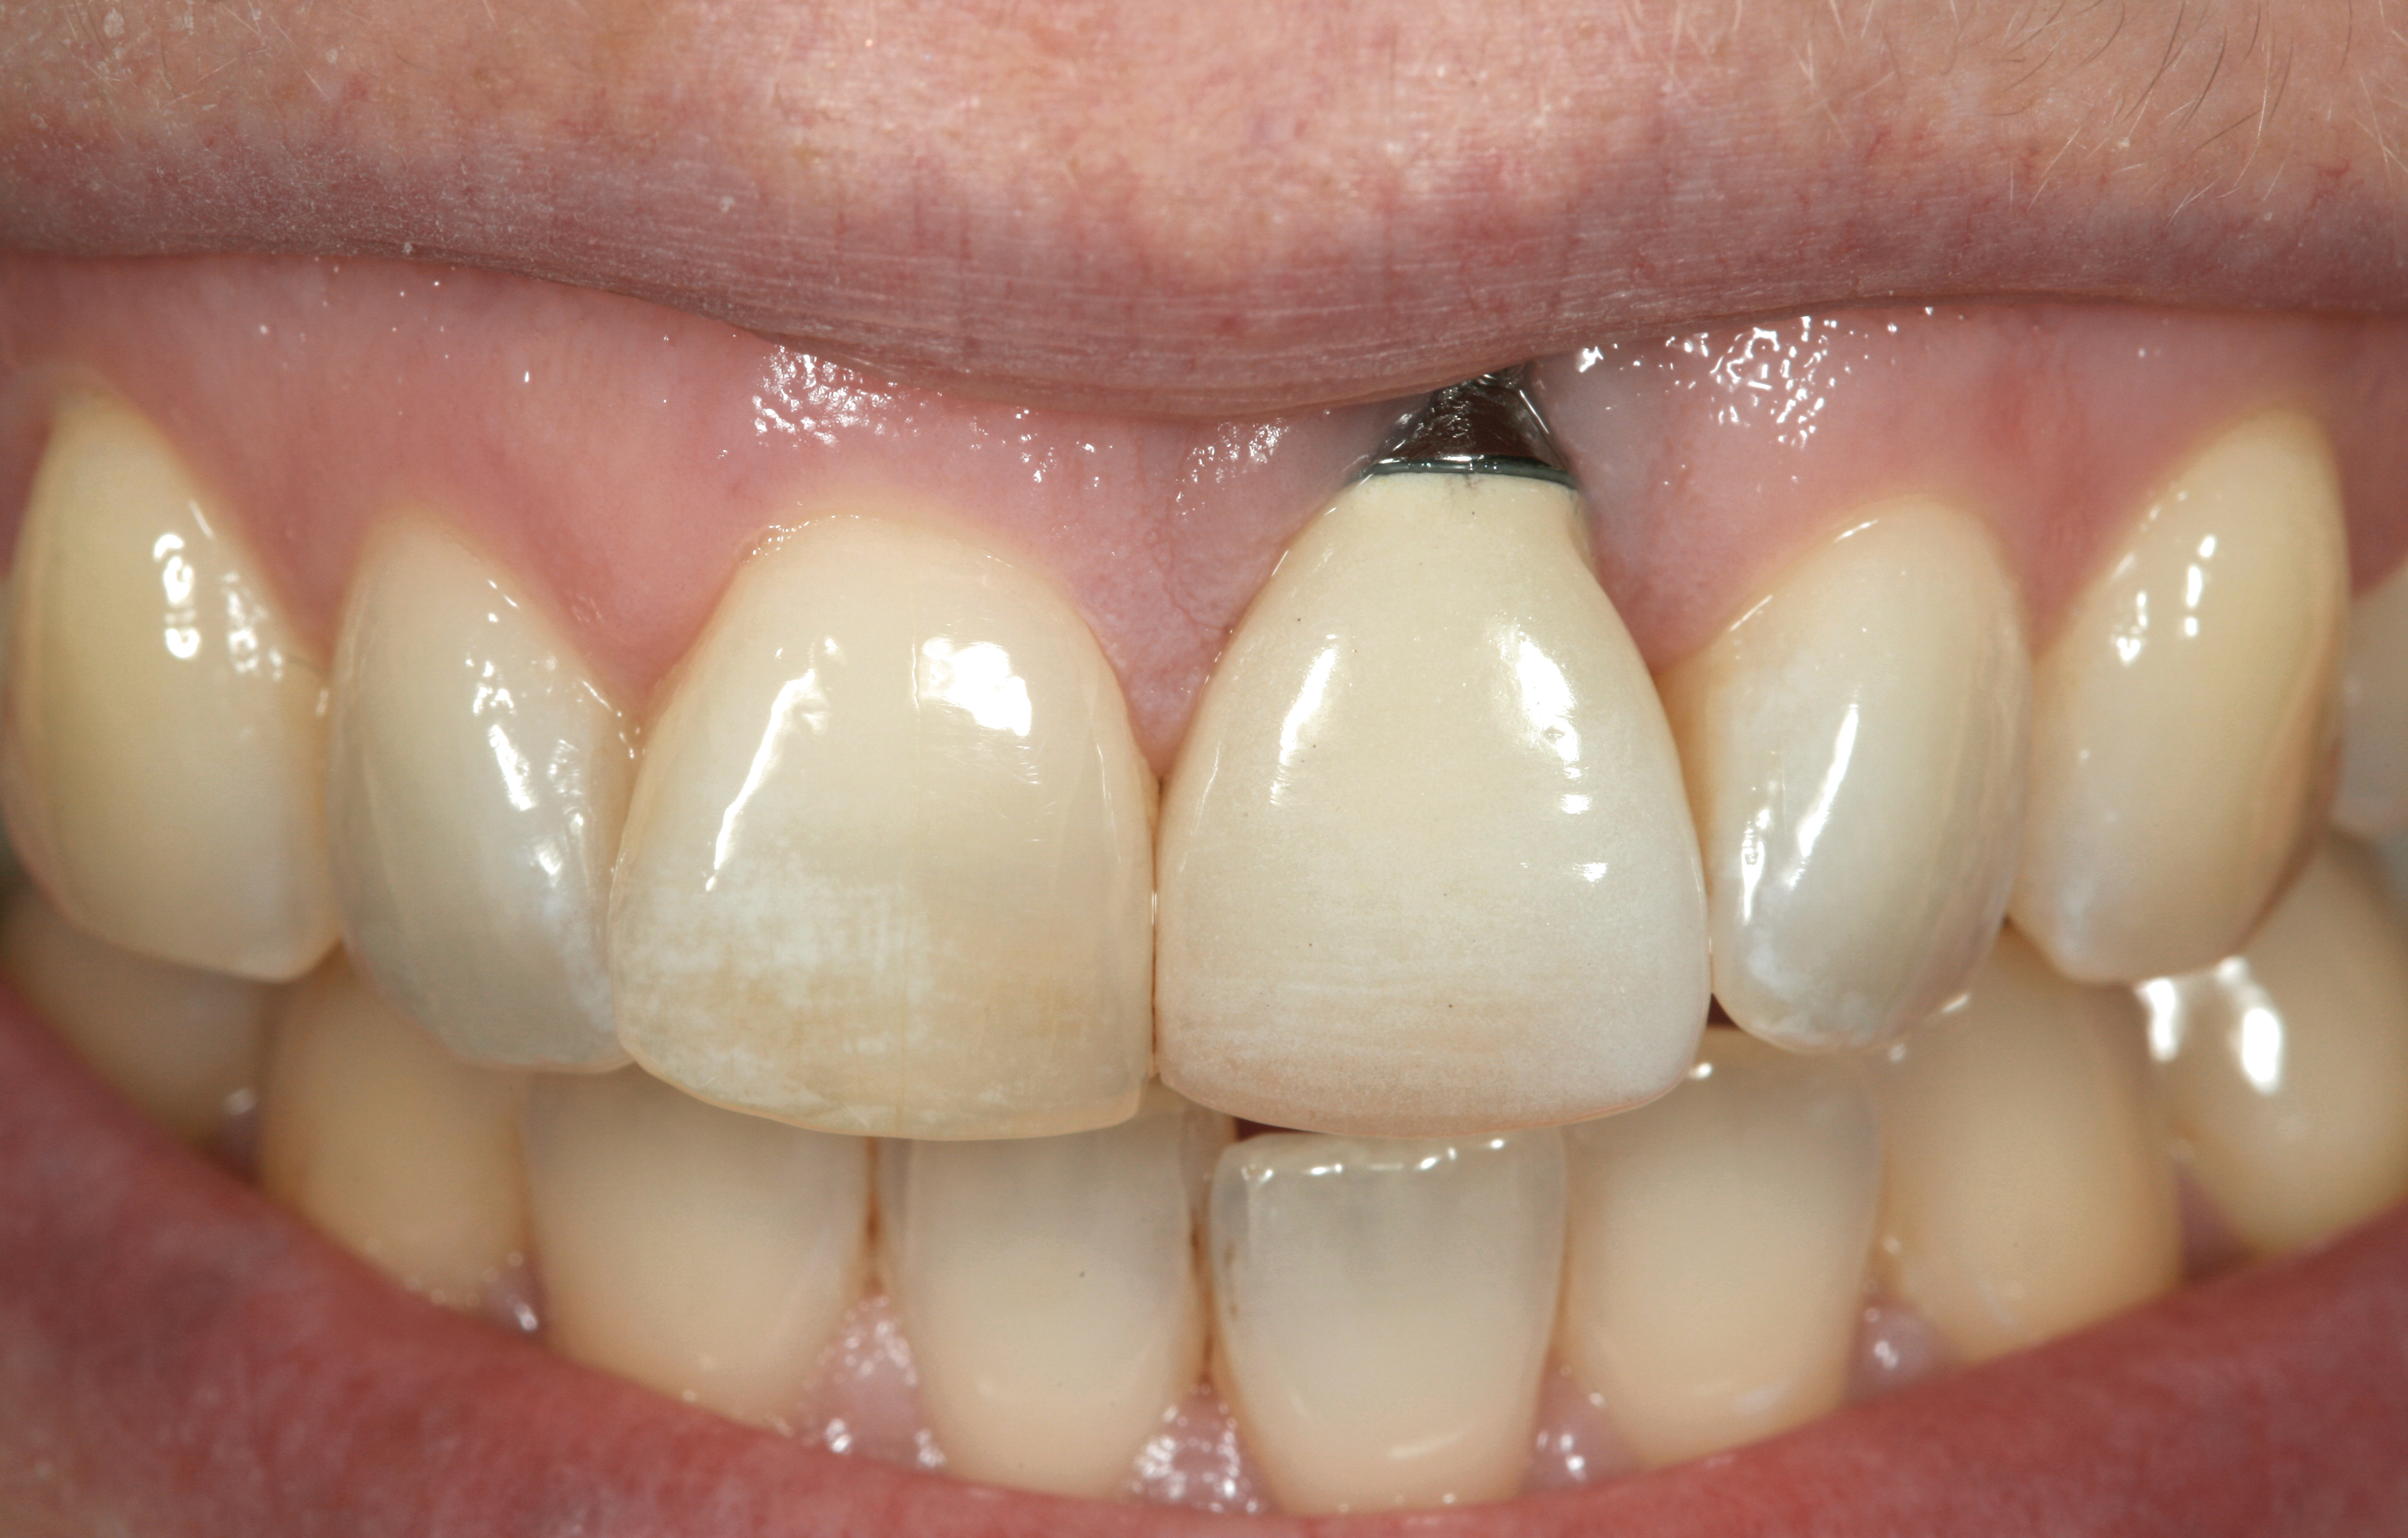

Fig 32. A dissatisfied patient presented with significant midfacial recession of implant restoration of tooth No. 26. Pink ceramic material was used unsuccessfully to prosthodontically compensate for the lost midfacial tissue.

Figure 32

Fig 36. Two weeks after RBR placement, the soft tissue did not adequately cover the implant. The problem was in poor implant angulation and proper depth to allow the soft tissues to cover over.

Figure 36